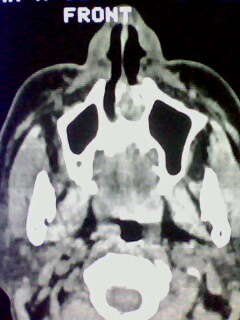

以下是引用随光逐影在2009-5-20 19:22:00的发言:[br]1)考虑左上颌骨近中线区含牙囊肿。2)鼻中隔右突偏曲。3)双侧下鼻甲肥大。